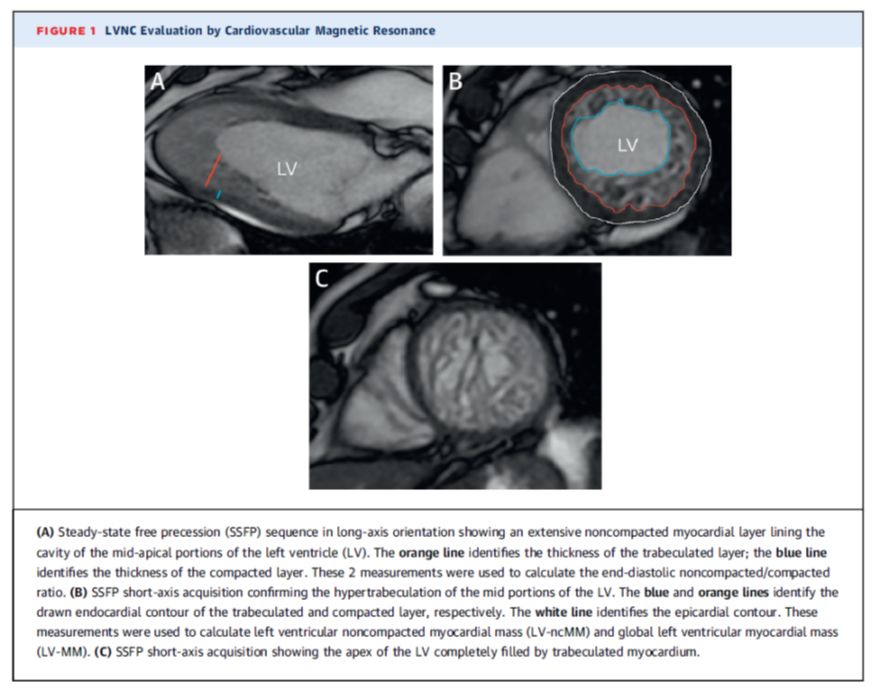

✦ 若根据超声心动图表现不能确定诊断,可使用CMR

✦ CMR可为左室所有节段提供良好的空间分辨率,包括心尖部和侧壁。

(2) 在舒张末期左心室长轴位, 非致密化心肌层厚度与致密化心肌层厚度之比>2.3。发现其诊断LVNC的敏感性为86%,特异性为99%。

✦ 一项研究纳入了16例LVNC患者、16例肥厚型心肌病和16例对照受试者,左心室小梁化质量占左心室总质量的比例大于20%被确定为LVNC的诊断标准。该度量标准的敏感性为94%,特异性为94%。

✦ 作为定量测定小梁化的方法,分形维数在LVNC患者中的值较高,且结果可能十分准确并具有可重复性。然而,健康黑人个体的左心室心尖1/3段的分形维数高于白人。

✦ 一项在16例LVNC患者中比较CMR和超声心动图的小型研究表明了这一点。在舒张末期CMR与超声心动图无差异。与CMR相比,超声心动图在收缩末期低估了心肌NC:C比值。